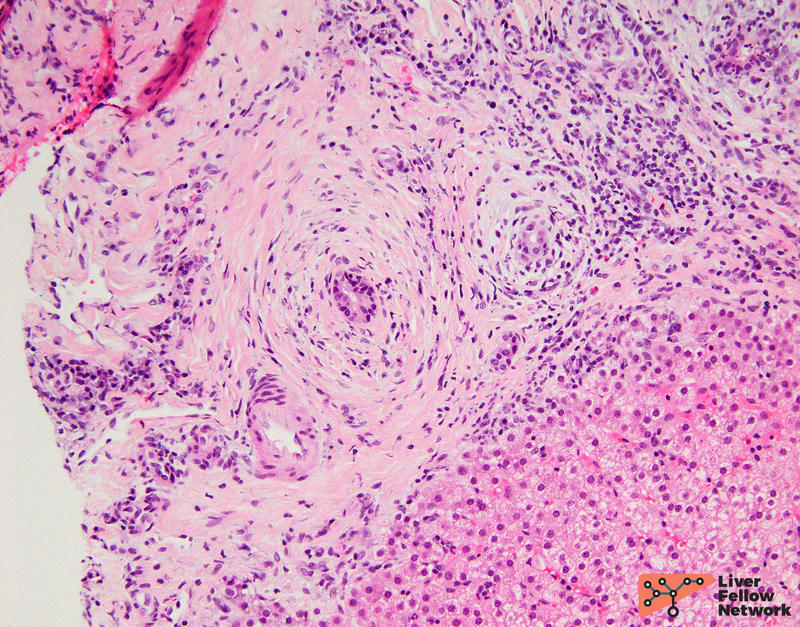

One portal tract reveals bile ducts surrounded by concentric fibrosis (Figure 3).

Figure 3a. Portal tract with scattered inflammation and concentric fibrosis.

Figure 3b. Higher magnification showing increased portal fibrosis.

The most classic findings of PSC include large bile ducts surrounded by concentric fibrosis, which is also referred to as “onion skin” fibrosis (Figure 7).

Figure 7. Concentric / "onion skin" fibrosis surrounding a bile duct.